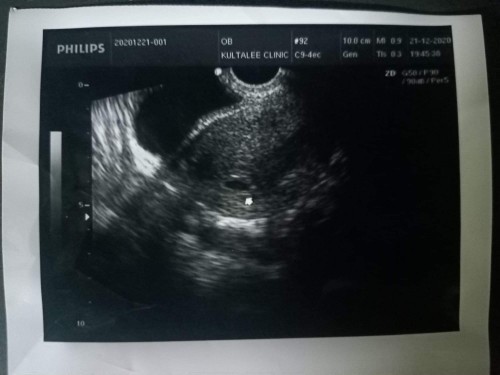

ท้องแรกค่ะ

คุณแม่คนไหนกำลังเป็นถุงตั้งครรภ์เหมือนกันบ้างคะ คุณหมอบอกว่า ท้องในมดลูก100%คุณหมอนัดอีกทีสามอาทิตย์ หลังปีใหม่ เพื่ออัลตร้าซาวดูว่า มีความเปลี่ยนแปลงอย่างไร ท้องลมหรือไม่ ลุ้นมากเลยค่ะ

ตอน7w ซาวด์เจอแต่ถุงตั้งครรภ์เหมือนกันค่ะ หมอนัดมาซาวด์อีกทีตอนน11w น้องเป็นตัวแล้วจ้า สู้ๆนะคะคุณแม่

กำลังเป็นถุงการตั้งครรภ์เหมือนกันจ้า อีก 1เดือนนัดอัลตราซาวน์ดูอีกรอบค่ะ

เราคะ7w+4dเห็นแค่ถุงตั้งครรภ์เล็กๆรอซาวอีกรอบหลังปีใหม่ กังวลมากๆ

เราค่ะ..มีถุงไข่แดงแล้วแต่ยังไม่เห็นน้องเลย หมอนัด 28/12/63 ค่ะ

ตอนน้องเราเป็นท้องลม ก็ไม่มีเลือดออกไม่มีอาการอะไรเลยจ้า แต่ถ้าถุงตั้งครรภ์ใหญ่มากแล้วไม่มีตัวเด็กก็คงต้องลุ้นอีกทีค่ะ ไม่ทราบว่าตรวจทางหน้าท้องหรือช่องคลอดคะ

รูปนี้ตอนกี่วีคคะแม่

รูปนี้ซาวตอนกี่วีคคะ